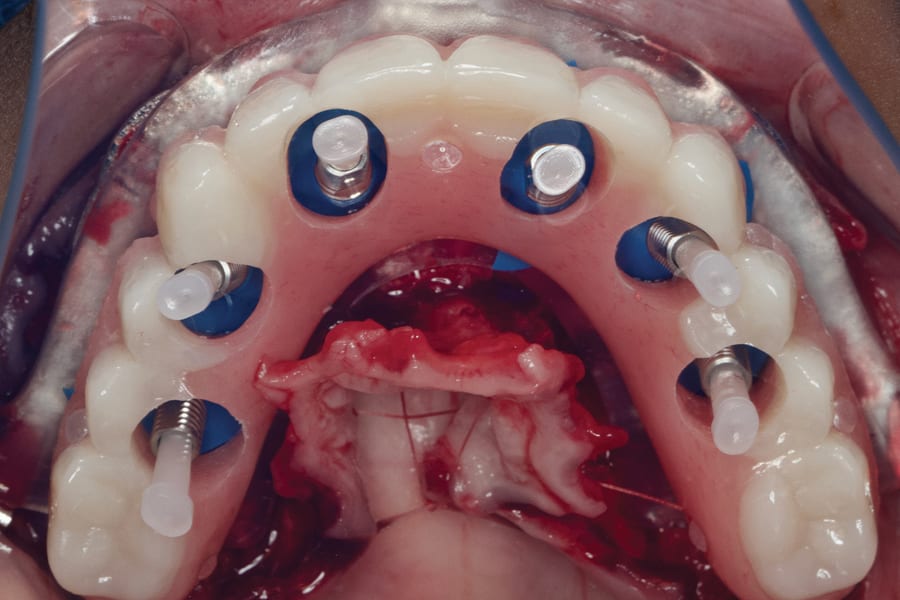

A 3D-printed metallic bone reduction guide is screwed to the jawbone (Figure 3) once its intended orientation has been determined using the occlusal indexing guide, which is used to ensure that the bone reduction guide is fixated in the correct position. The occlusal indexing guide is stabilized in the incisal and occlusal surfaces of the existing teeth. After completion of the bone reduction and extractions, an osteotomy guide is secured onto the metallic reduction guide for exacting, fully guided implant placement (Figure 4).

The clinician has the option to perform a simple polymethyl methacrylate (PMMA) conversion to allow the patient to leave the appointment with a fixed provisional and a new smile on the day of the surgery (Figure 5). As an alternative to a chairside pickup, a photogrammetry digital impression of the implants can be made and shared with the laboratory for immediate design of the fixed provisional, which can then be 3D-printed in-house. This approach is becoming more common, as a high percentage of dental clinics performing full-arch prostheses are equipped with 3D printers.